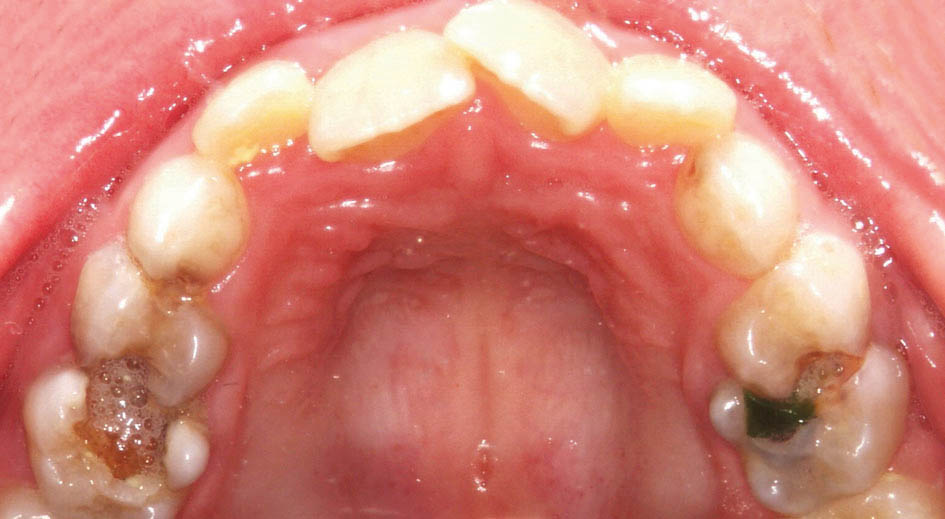

بعضی موقع چند مشکل را با هم در یک کودک میبینید. مثلاً بیمار کراس خلفی یک طرفه و کراس قدامی (شکل 36-5 و 37-5) دارد.

شکل 36-5: کراس بایت خلفی در سمت چپ

شکل 37-5: سمت راست کراس بایت خلفی ندارد پس کودک کراس بایت خلفی یک طرفه دارد.

از آنجایی که دندانهای خلفی بالا تیلت پالاتالی ندارند(شکل38-5) و میدلاین دندانی و چانه بیمار (شکل39-5 و40-5) به چپ منحرف است به کراس دو طرفه و انحراف طرفی مندیبل پی میبریم.

از طرفی انسیزورهای بالا در کراس هستند (شکل 39-5) پس به انحراف قدامی مندیبل هم شک میکنیم

شکل 38-5: تقارن قوس بالا نشان دهنده دو طرفه بودن کراس است و بخاطر انحراف مندیبل یک طرفه دیده میشود.